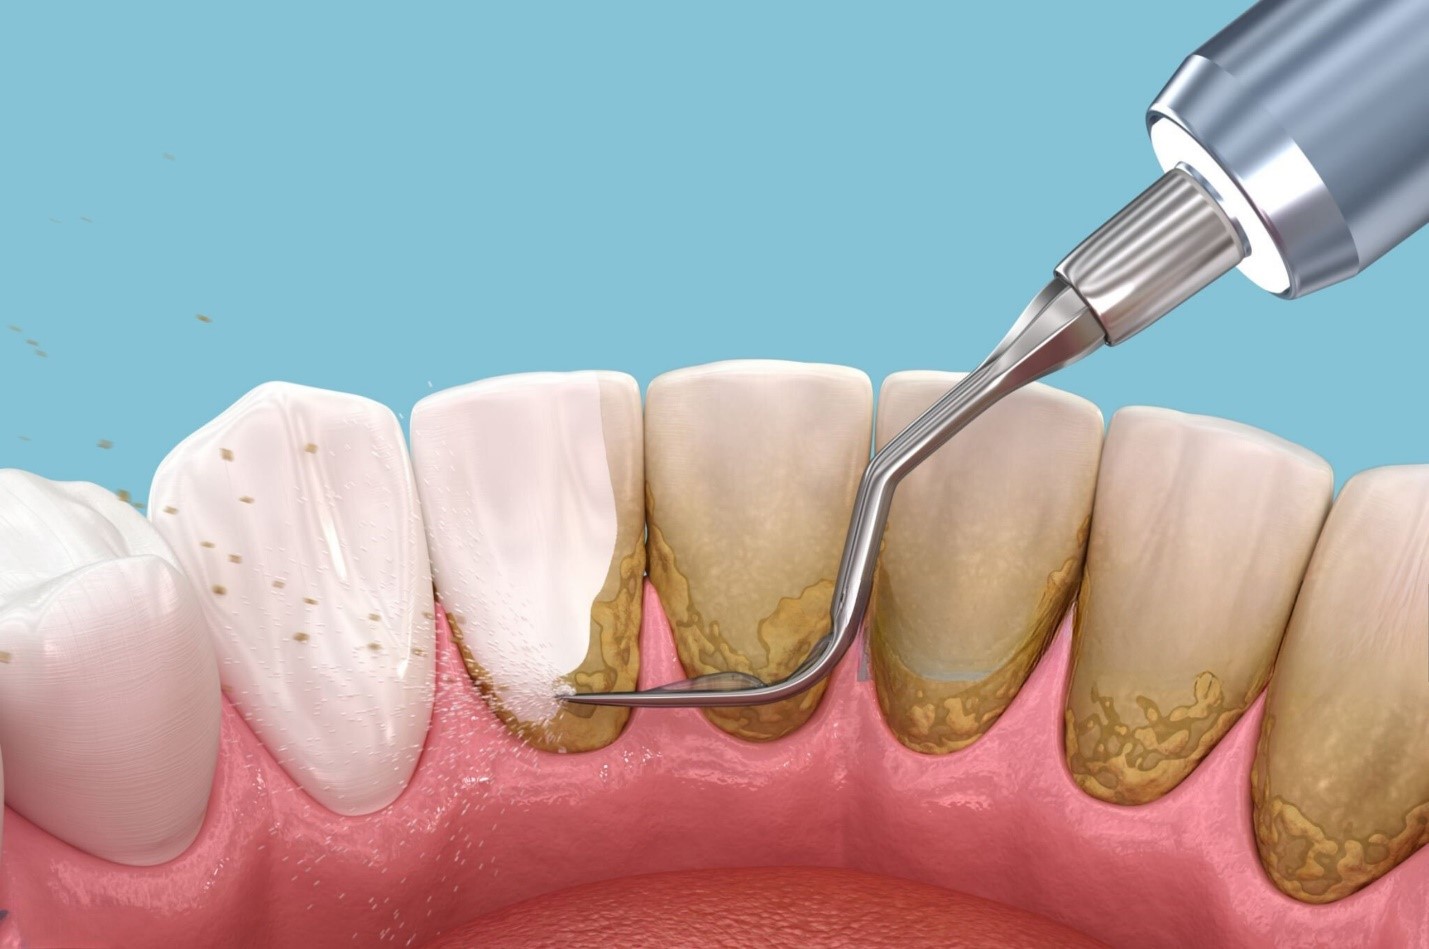

Cặn thức ăn và vi khuẩn tích tụ lâu ngày sẽ tạo thành mảng bám, sau đó khoáng hóa thành cao răng. Cao răng thường có màu vàng nâu hoặc đen, bám chặt ở răng hàm – nơi khó vệ sinh.

- Lấy cao răng và đánh bóng: Đây là bước cơ bản và cần thiết. Việc loại bỏ mảng bám và cao răng cứng đầu giúp loại bỏ vết ố đen do vi khuẩn hoặc khoáng hóa. Sau đó, đánh bóng sẽ làm mịn bề mặt răng, giảm khả năng bám dính của các chất tạo màu.

- Lấy cao răng bằng máy siêu âm: Nhanh chóng, không đau, loại bỏ triệt để mảng bám.